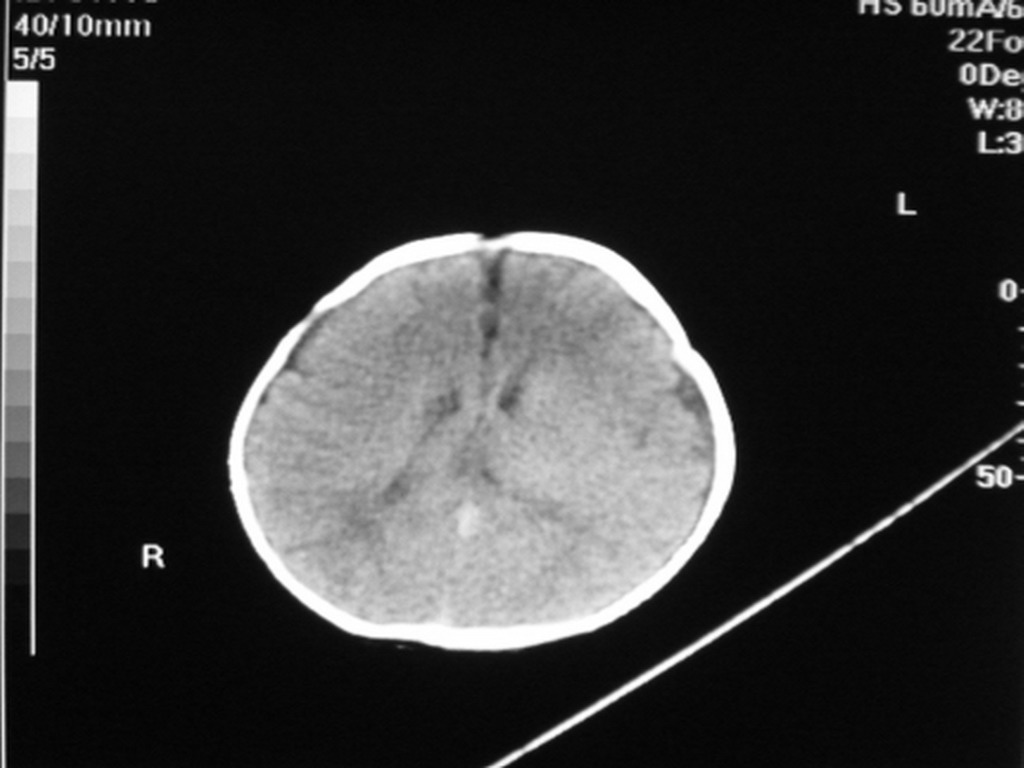

标题: PED1877:女,20余天,突发抽搐,双眼凝视。 [打印本页]

女,20余天,突发抽搐,双眼凝视。